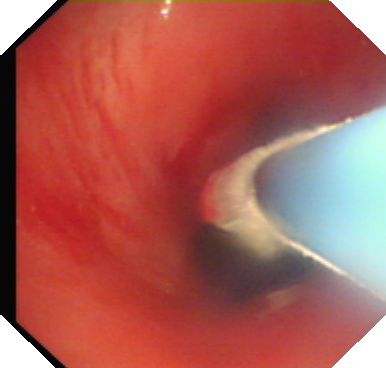

经治疗后目前患者恢复良好,准备下一阶段的气切口封闭中。

(气管内大部分肉芽组织被清除,管腔变通畅)